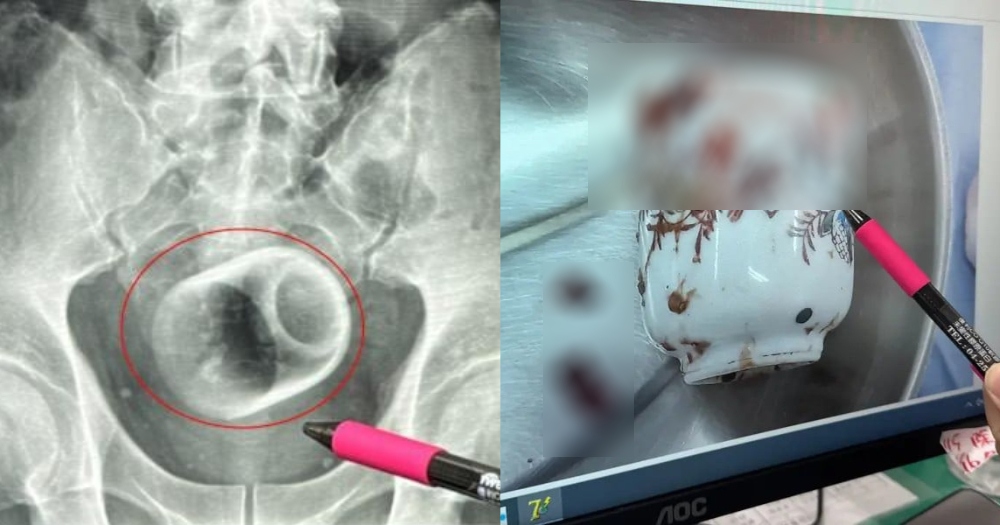

Các bác sĩ phát hiện chiếc cốc trong cơ thể người đàn ông.

Ông đã không đề cập đến sự hiện diện của chiếc cốc với các bác sĩ trước đó vì quá xấu hổ. Kết quả chụp X-quang cho thấy chiếc cốc úp ngược trong khoang chậu.

Trong phòng mổ, các bác sĩ đã thử sử dụng các dụng cụ, bao gồm cả ống nội soi, để lấy cốc ra. Nhưng điều đó vô ích vì chiếc cốc quá trơn.

Cuối cùng, họ đã lấy chiếc cốc ra bằng một cuộc phẫu thuật mở ở bụng người đàn ông, đồng thời tạo ra một lỗ thông nhân tạo để người này có thể đại tiện.